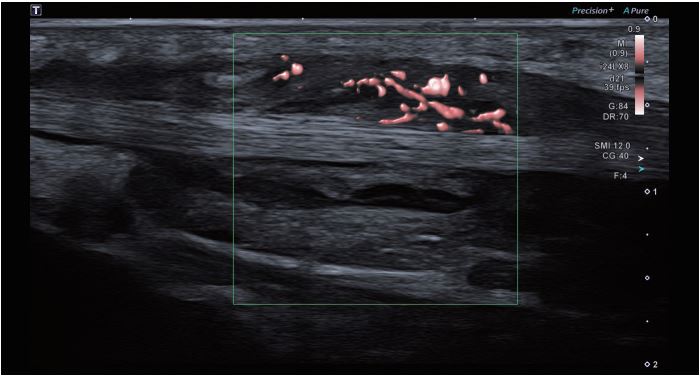

Зображення 3 Демонструється підвищена васкуляризація. SMI допомагає виявити і продемонструвати деталі дрібних судин в області зацікавленості.

Зображення 4 Поздовжня томограма з SMI демонструє

виражену гіперваскуляризацію ушкодженої ділянки.